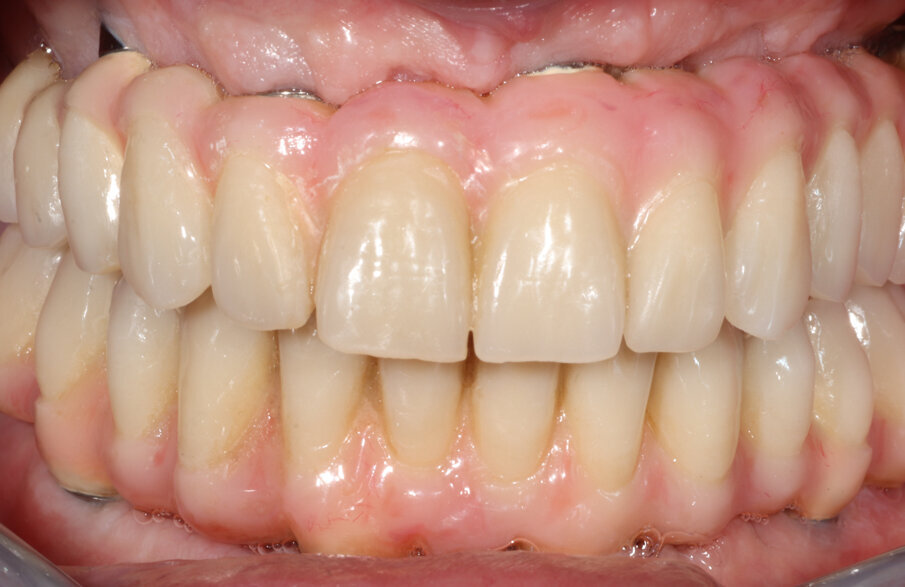

Una volta verificata l’osteointegrazione degli impianti si è passati alla fase finale della riabilitazione protesica. La dimensione verticale è stata, a questo punto, modificata mediante incrementi occlusali progressivi fino al raggiungimento di un’altezza perfettamente bilanciata e confortevole per il paziente. La riabilitazione protesica definitiva è stata quindi realizzata dal laboratorio con una struttura costituita da due barre in titanio, al di sopra delle quali sono stati incollati denti in composito (neo.lign, bredent). Anche la modellazione della porzione gengivale del rivestimento protesico è stata realizzata in composito (crea.lign, bredent). La protesi definitiva in titanio-composito è stata infine consegnata al paziente (Figg. 9-10b).

Fig. 9_La protesi definitiva.